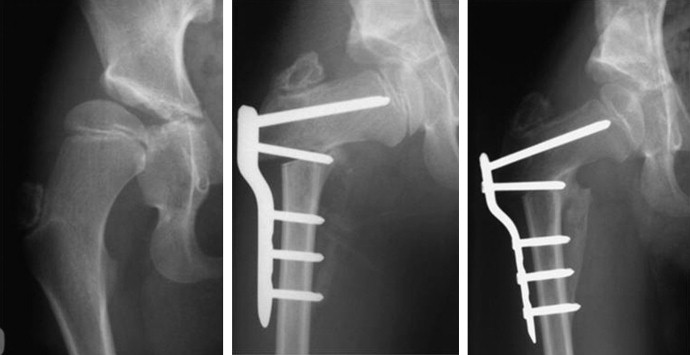

Proximal femur osteotomy

Proximal femur osteotomy technique

Proximal femur osteotomy result